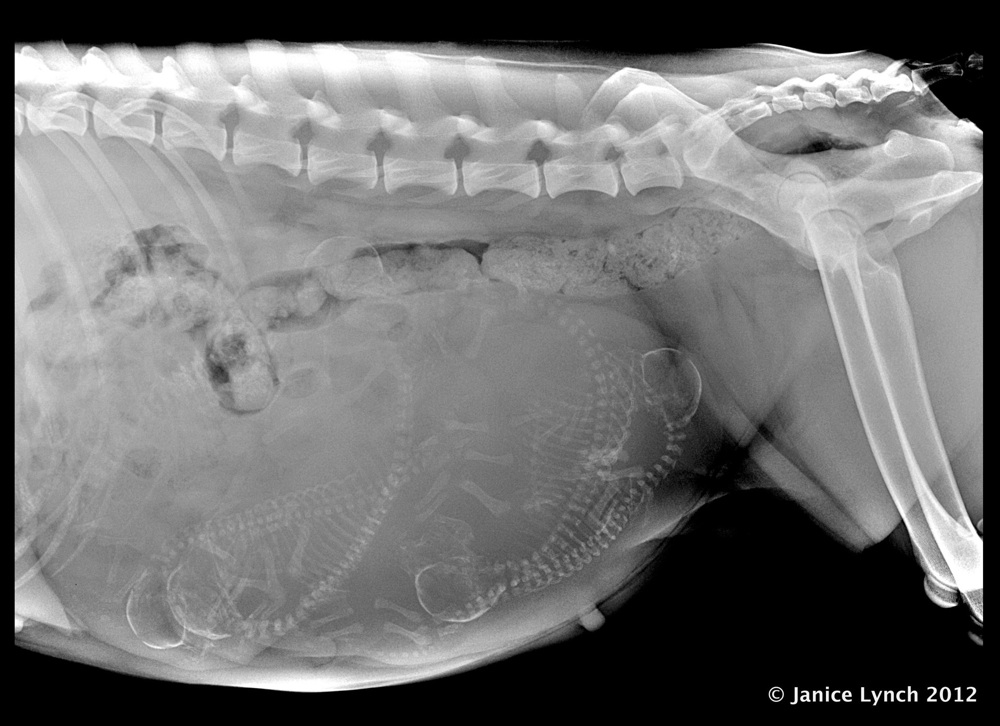

Samoyed testing currently focuses on three areas:  hips, eyes, heart.  Hips:  according to the Samoyed Club of America (SCA), prior to breeding the sire and dam should be evaluated via a hip radiograph (x-ray) submitted to OFA or PennHip.  Hip dysplasia is an inherited, polygenic disease in which the ball and socket joint is malformed.  It can be extremely painful and debilitating.  Early onset hip dysplasia can present in young dogs, usually after four months of age.  Symptoms can present later in the dog’s life, due to osteoarthritis.  Eyes:  SCA advises that all Samoyeds who are going to be bred should have their eyes tested annually, by a veterinary ophthalmologist.  SCA also advises that all Samoyeds who are going to be bred should also undergo the genetic screens for x-linked progressive retinal atrophy (PRA) and retinal dysplasia/OSDCardiac:  SCA advises that, prior to breeding, all sires and dams be evaluated by a veterinary cardiologist to minimize the risk of passing on congenital cardiac abnormalities to their offspring.

2. Hips - OFA, OVC or PennHIP evaluation